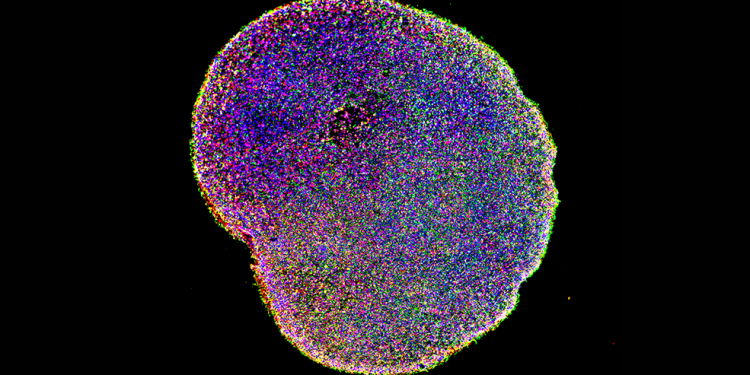

In pratica, secondo la ricercatrice italiana, si è riusciti a creare dei mini-cervelli che abbiano caratteristiche uguali tra loro permettendo una sperimentazione che parta dagli stessi punti in comune. Questi piccoli organi crescono in provetta, generati da cellule staminali, e fino ad oggi si sviluppavano ognuno con caratteristiche differenti dall’altro. È l’uniformità delle cellule però il requisito fondamentale per effettuare dei test efficaci.

Ed è qui che il team guidato da Arlotta è intervenuto, creando un metodo realmente efficace per donare quell’uniformità a tutti gli organoidi creati in provetta. «In questo studio dimostriamo che un modello organoide del proencefalo dorsale può generare in modo affidabile una ricca diversità di tipi cellulari appropriati per la corteccia cerebrale umana – afferma lo studio pubblicato su Nature – Abbiamo eseguito un’analisi del sequenziamento dell’RNA di 166.242 cellule isolate da 21 singoli organiidi, trovando che il 95% degli organiidi genera un compendio praticamente indistinguibile dei tipi di cellule, seguendo traiettorie di sviluppo simili e con un grado di variabilità da organoide a organoide paragonabile a quella dei singoli cervelli endogeni».